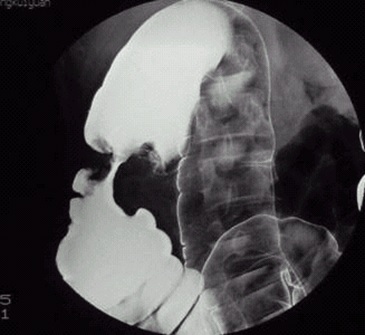

05卷-3.病史:女性,52岁,触及腹部包块3周。诊断(本题满分2.00分)

本题答案:B

题目解析:【该题针对“造影-结肠癌”知识点进行考核】